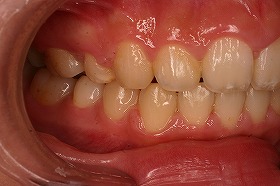

この症例は、出っ歯を矯正治療でキレイにしたケースです。

最初にいらしたときには、出っ歯であることによって

噛み合わせが上手くいかず、口を閉じることが出来ないケースでした。

この場合だと、噛み合わせが悪いだけでなく、

口が常に開いているために、見た目もだらしなくなってしまいます。